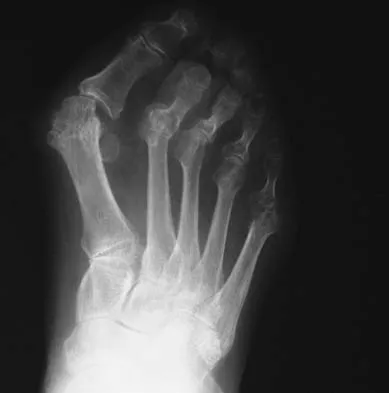

An active 47-year-old woman with rheumatoid arthritis reports forefoot pain and deformity and has difficulty with shoe wear. Examination reveals hallux valgus and claw toes. A radiograph is shown in Figure 10. What is the most appropriate surgical treatment?

Explanation

Rheumatoid arthritis commonly affects the metatarsophalangeal joints, which become destabilized with time resulting in hallux valgus and dislocated lesser claw toes. The result is metatarsalgia as the dislocated claw toes "pull" the fat pad distally. Severe hallux valgus reduces first ray load, which compounds the metatarsalgia because the load is transferred to the lesser metatarsal heads. First metatarsophalangeal arthrodesis restores weight bearing medially and corrects the painful bunion. Metatarsal head resection slackens the toe tendons to allow correction of the claw toes by whatever means necessary and decreases plantar load over the forefoot. Rheumatoid arthritis in the first metatarsophalangeal joint will continue to progress if osteotomies or a Lapidus procedure are performed. Keller resection arthroplasty increases transfer metatarsalgia and reduces push-off power during gait. Flexor-to-extensor tendon transfer of the lesser toes does not address the metatarsalgia and does not correct the dislocation of the metatarsophalangeal joint. Coughlin MJ: Arthritides, in Coughlin MJ, Mann RA (eds): Surgery of the Foot and Ankle, ed 7. St Louis, MO, Mosby, 1999, p 572.